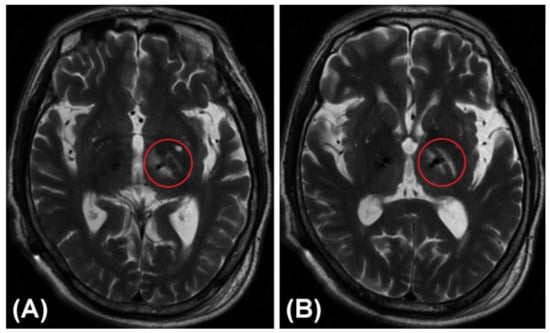

Figure 5 shows a rare non-hemorrhagic edematous lesion around the trajectory in the trajectory planning group. An electrode placed for the left STN through the PLIC led to local edema of the PLIC and adjacent white matter (i.e., the medial medullary lamina), which appeared similar to a “hamburger”, together with the relatively normal GPi. These images were taken from a 71-year-old male patient with PD 3 days after he received bilateral lead placement in the STN. He suffered from transient urinary incontinence and mild weakness of the right limbs after the DBS operation.

Figure 5.

A rare non-hemorrhagic edematous lesion or infarction around the trajectory in a T2-weighted MRI image. An electrode placed for the left STN through the PLIC led to local edema of the PLIC and adjacent white matter (i.e., the medial medullary lamina), which appeared similar to a “hamburger”, together with the relatively normal GPi. (A) Lower layer. (B) Upper layer.